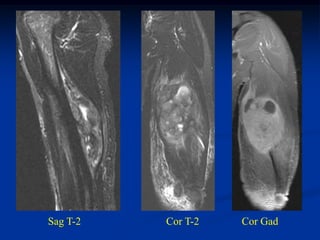

Sagittal T-2 MRI 18 months later with desmoid tumor

Axial T-2 MRI at 18 months

Photomic

Post op resection

distal ulna with

synostosis of distal

ulnar tip to radius